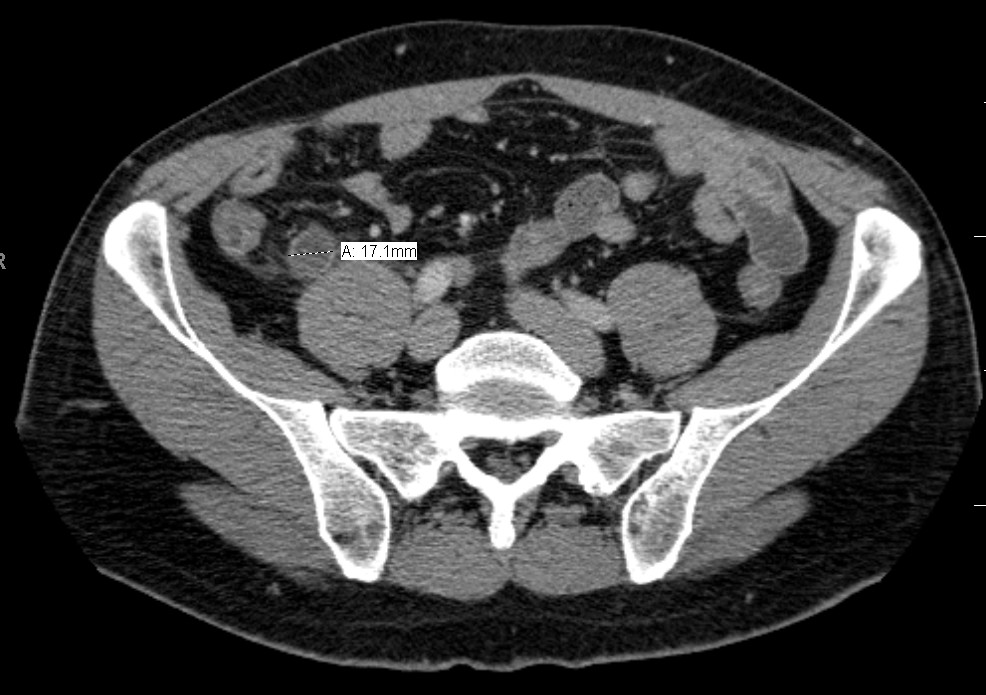

CT 스캔은 급성 충수염을 진단하는데 사용된다.[36] 의사는 환자의 병력과 증상을 평가하고, 신체 검사를 시행하며, 검사실 및 영상 검사를 모두 주문한다. 비전형적인 증상을 보이는 경우에는 초음파나 CT 스캔과 같은 영상 검사가 필요하다.[12] 소아는 방사선 노출 위험 때문에 초음파 검사를 우선적으로 시행하며, 결과가 불확실한 경우에만 CT 스캔을 추가로 시행한다.[54][55][56] 성인 및 청소년의 경우 CT 스캔이 초음파 검사보다 더 정확하며, 민감도 94%, 특이도 95%를 보인다. 반면 초음파 검사는 민감도 86%, 특이도 81%이다.[57]복부 초음파 검사, 특히 도플러 초음파는 특히 소아에게서 충수염 진단에 유용하다. 초음파 검사에서는 오른쪽 장골와에서 액체 저류, 컬러 도플러 사용 시 혈류 증가, 충수의 비압착성 등이 관찰된다. 급성 충수염의 다른 징후로는 충수 주변의 에코성 장간막 지방, 충수 결석의 음향 그림자 등이 있다.[58] 약 5%의 경우, 장골와 초음파 검사에서 이상이 발견되지 않지만, 이는 초기 충수염이거나 지방과 장내 가스로 인해 충수 확인이 어려운 성인에게서 흔하게 나타난다. 숙련된 검사자는 초음파 영상을 통해 충수염과 유사한 증상을 보이는 림프절 염증, 난소 또는 나팔관 문제 등을 구별할 수 있다.[60] 초음파 검사는 방사선과나 응급 의학 전문의가 시행할 수 있다.

충수염 진단은 충수 크기가 가장 중요하며, 6mm 이상이면 민감도와 특이도가 모두 95%이다.[65] 그러나 충수가 분변 물질로 채워져 팽창된 경우에는 진단이 어려울 수 있다.[66] 이 경우 초음파 검사가 유용하며, 주변 장에 비해 벽의 조영 증강, 주변 지방 염증 등의 특징으로 진단을 돕는다. 심한 경우 농성 염증, 고름집, 고름이나 장 내용물 누출로 인한 골반 내 액체 층이 관찰될 수 있다. 마른 환자는 지방 부족으로 충수와 주변 염증 관찰이 어려울 수 있다.[66]

CT 검사에서 충수 부종이나 주변 지방 조직 농도 상승이 관찰되며, 조영제 사용 시 민감도와 특이도가 모두 98%로 정확도가 높다. 최신 초음파 검사 장비는 맹장 형태 평가에 유용하지만, 맹장 위치나 장비, 검사자 숙련도에 따라 진단이 어려울 수 있다. 최근 소아 충수염 진단에서 컴퓨터 단층 촬영(CT) 검사는 감소하고 초음파 검사는 증가했지만, 임상 경과에는 변화가 없다는 보고가 있다.[126]